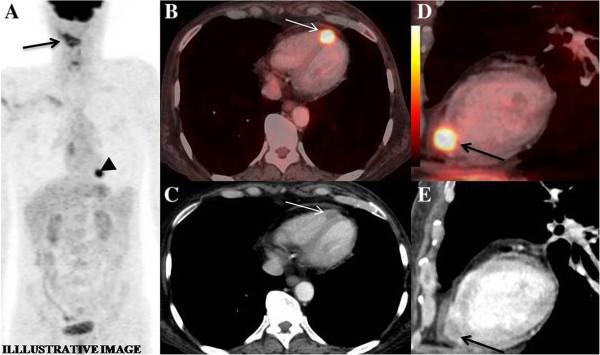

Metastatic involvement of the heart is a rare occurrence and remains undiagnosed until autopsy. In some instances, patients may have cardiac symptoms, leading to ante-mortem diagnosis. Although most primary cancers have been documented to metastasize to heart, the existing literature on cancers of upper aero-digestive tract is an exception, with only a few reports. We report four cases of upper aero-digestive tract cancers, three of which arise from oral cavity, one from lower esophagus, metastasising to the myocardium, detected on 18 F - Fluoro-deoxy-glucose Positron Emission Tomography/Computed Tomography (FDG PET/CT) study , in the absence of related symptoms.

心脏转移受累较为罕见,直至尸检时才得以诊断。在某些情况下,患者可能会出现心脏症状,从而得以生前诊断。尽管大多数原发性癌症都有转移至心脏的记录,但关于上消化道癌症的现有文献却是个例外,仅有少数报道。我们报告了4例上消化道癌症,其中3例起源于口腔,1例起源于食管下段,在没有相关症状的情况下,经18F-氟脱氧葡萄糖正电子发射断层扫描/计算机断层扫描(FDG PET/CT)检查发现转移至心肌。